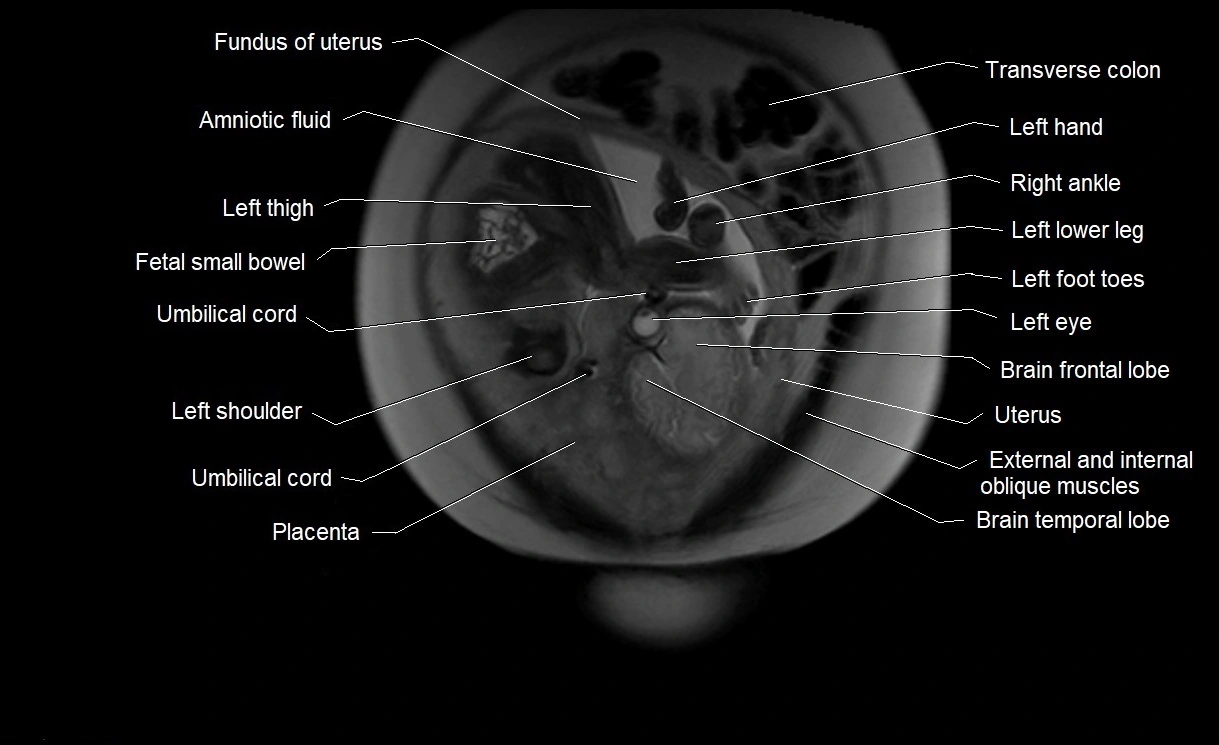

MRI Appearance

T2 HASTE (T2 GRE):

• Amniotic fluid shows very bright hyperintense signal

• Provides natural contrast against fetus and placenta

• Small particles (vernix) may appear as scattered hypointense foci within bright fluid

MRI image

image